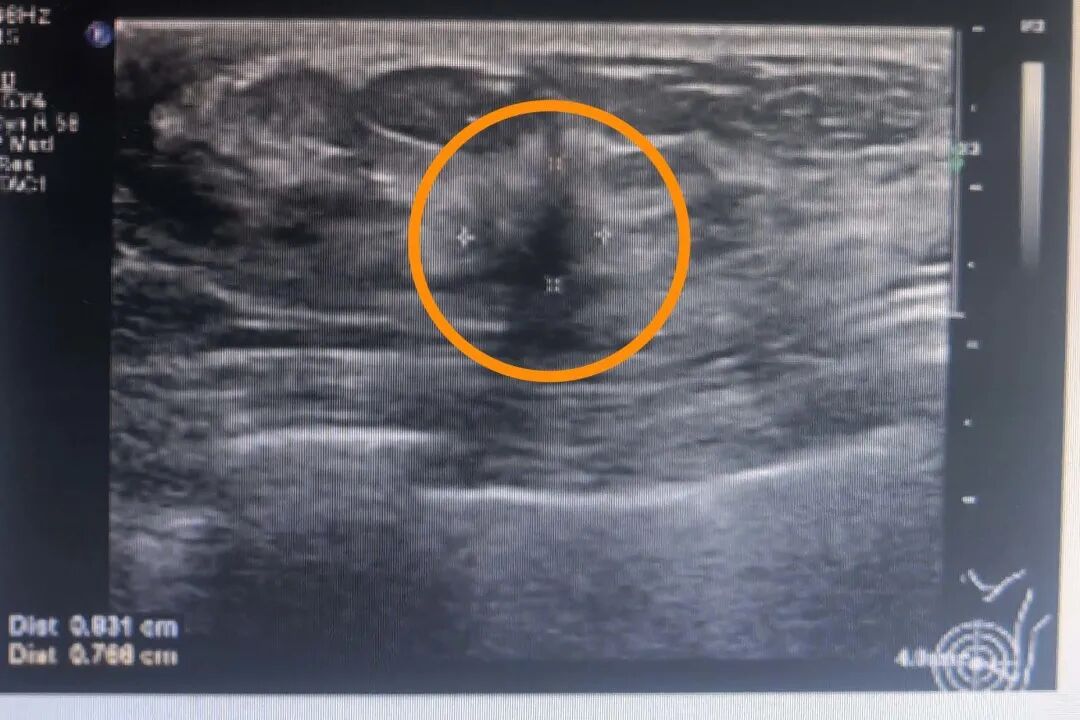

檢查的過程中,醫(yī)生對(duì)張女士的病情有了新發(fā)現(xiàn),并非只有一個(gè)病灶,而是在可觸及腫塊的周圍還有一個(gè)小的病灶。彩超顯示張女士左乳2點(diǎn)鐘方向可見一30×19×29mm的低回聲結(jié)節(jié),邊界不清,形態(tài)不規(guī)整,周邊有血流;另于左乳4點(diǎn)方向可見一8.3×7.7mm的低回聲結(jié)節(jié),邊界不清,形態(tài)不規(guī)整,周邊有血流。